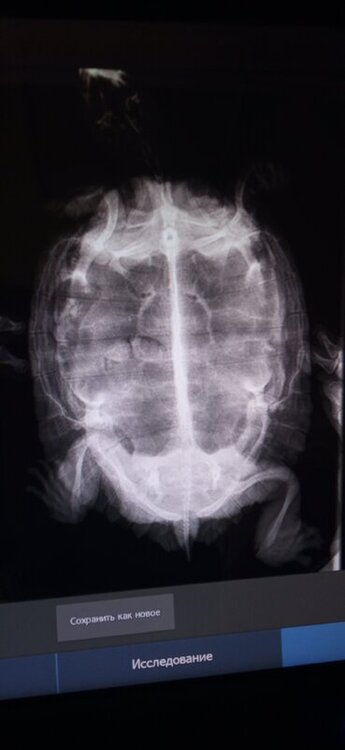

@moth здравствуйте, были сейчас у врача, сделали рентген, ето нему сказали что ни яиц, ни проблем с лёгкими нет, но есть инородное тело в кишечнике. Прописали 1,5 мм вазелинового масла в желудок, предположили ещё что глотка воспалена из-за этого белая плёнка выходит

IMG_20220409_134013.jpg

IMG_20220409_134011.jpg

Ещё порекомендоваои кальций проставить из-за ослабленных костей

ну и лёгкие по таким проекциям не смотрят

@OzzI1984 я покажу снимки нашему герпетологу, спрошу что там может быть, может это каловый завал, а не инородка.